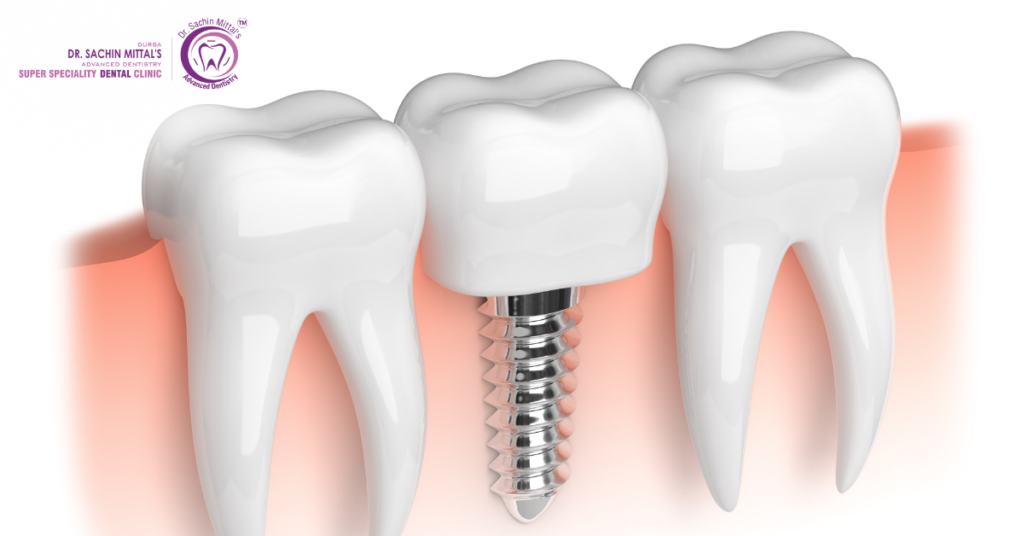

1. Dental Implants: A New Tooth That Feels Natural

Dental implants are used to replace a missing tooth. It looks and works just like a real tooth. In other countries, this treatment is very costly. In India, it is much more affordable, and the quality is very good.

Why NRIs Like It in India:

- Costs less than in other countries

- Dentists are well-trained and skilled

- Treatment is completed in a short time

- Implants last for many years if cared for properly